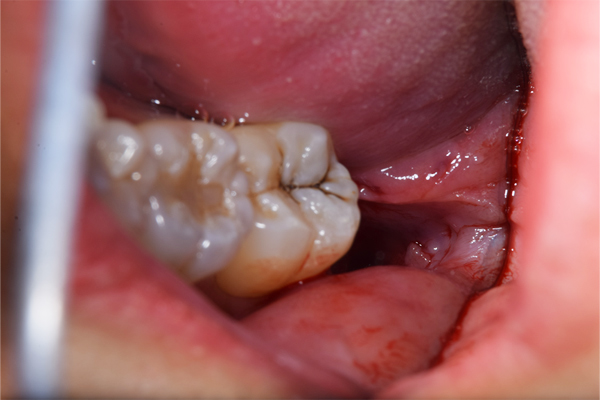

検査時のレントゲン写真です。

下顎の親知らずは右下のみはえています。まっすぐはえていますが、前の歯よりも低い位置にあるので、磨くのが難しそうです。舌側の歯茎がかぶっているのがみてとれます。

上顎の親知らずは頬の方を向いてはえています。こういうった親知らずはやはり磨くのがとても難しいです。